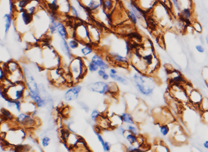

碳酸酐酶(CAs)是一类含锌金属酶大家族,可催化二氧化碳的可逆水合反应,参与呼吸、钙化、酸碱平衡、骨吸收以及房水、脑脊液、唾液和胃液生成等多种生理过程。这类酶在组织分布和亚细胞定位上具有高度多样性。碳酸酐酶9(CA9)是其中唯一的肿瘤相关异构酶,属于跨膜蛋白。它在所有透明细胞肾细胞癌中均表达,但在正常肾脏及绝大多数正常组织中不表达,可能与细胞增殖和转化相关。CA9被认为是许多实体瘤中缺氧区域的最佳细胞标志物之一。

阳性部位:

细胞膜